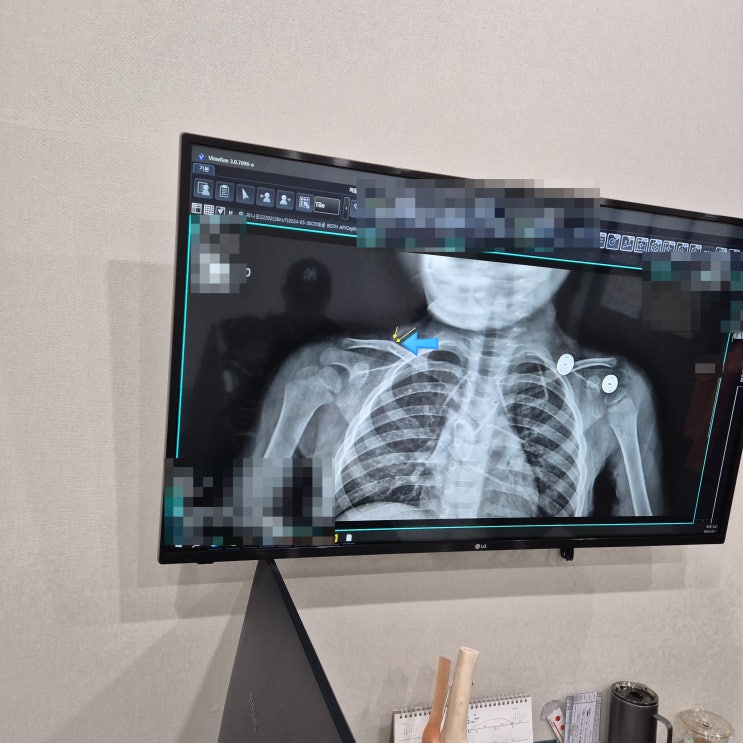

29개월 낙상 쇄골 골절 후 2주차 진료

28개월 아기 낙상쇄골 골절 후 1주차 진료

관련정보 28개월 아기 낙상 쇄골 골절 후 1주차 진료 ⓒ여낙낙 https://blog.naver.com/jhyeo1126/22345922...